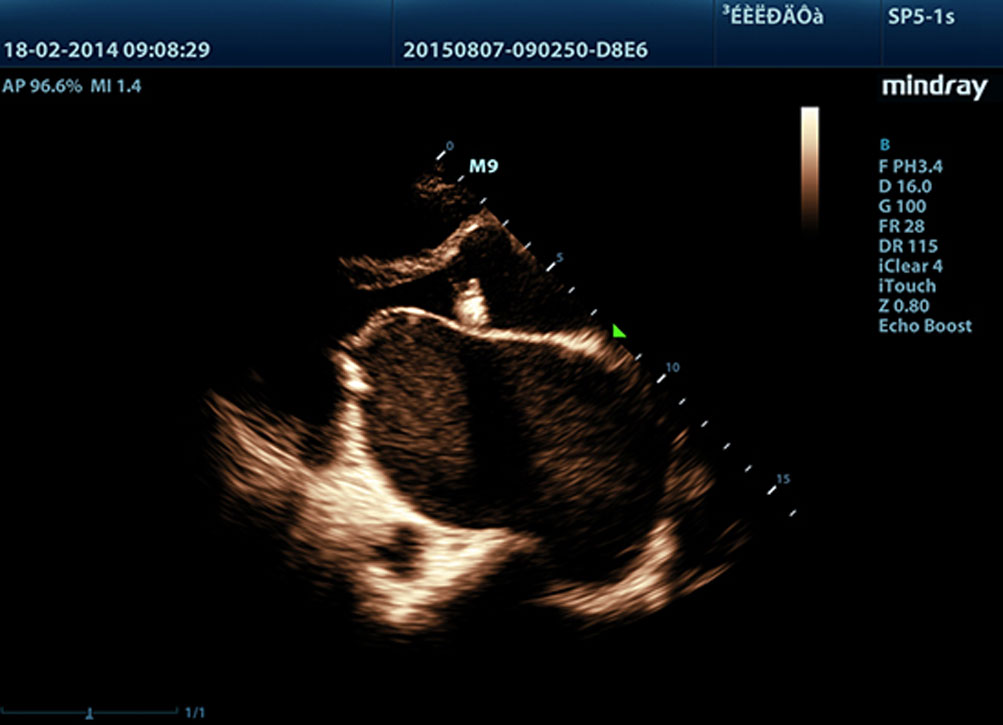

Echo Boost?

Teknologi pemrosesan sinyal adaptif Mindray yang unik dengan deteksi gema pintar, dirancang agar menggunakan informasi sinyal-ke-noise asli untuk menyempurnakan sinyal gema yang lemah sekaligus mengurangi suara bising di sekitar. Dengan demikian, dapat dihasilkan kecerahan gambar yang lebih seimbang dan visualisasi lapisan jaringan miokardium yang lebih baik.